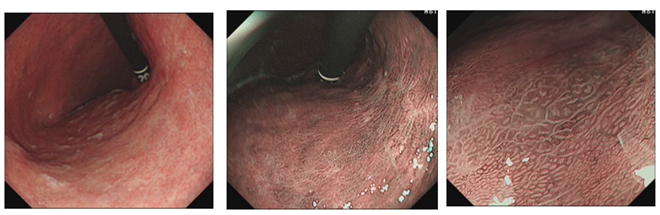

复原图如下:

该患者为Hp感染后萎缩性胃炎背景下胃体小弯侧0-Ⅱb型病变,白光下可见胃体小弯侧平坦型病变,色泽以红为主,边界较清晰,表面伴有轻微隆起的颗粒样结节,反复吸气充气后病变延展性好,黏膜轻微增厚,并且无明显凹陷及隆起,无皱襞集中表现,故深度考虑为黏膜内癌;M-NBI下MS可见不规则卵圆形腺管结构,呈绒毛状,无融合,MV可见不规则扭曲,粗细不均的血管局限于卵圆形腺管内(VEC),故分化类型考虑,分化型为主(乳头状腺癌),伴有少量低分化腺癌可能。结果从病理活检中得以证实。